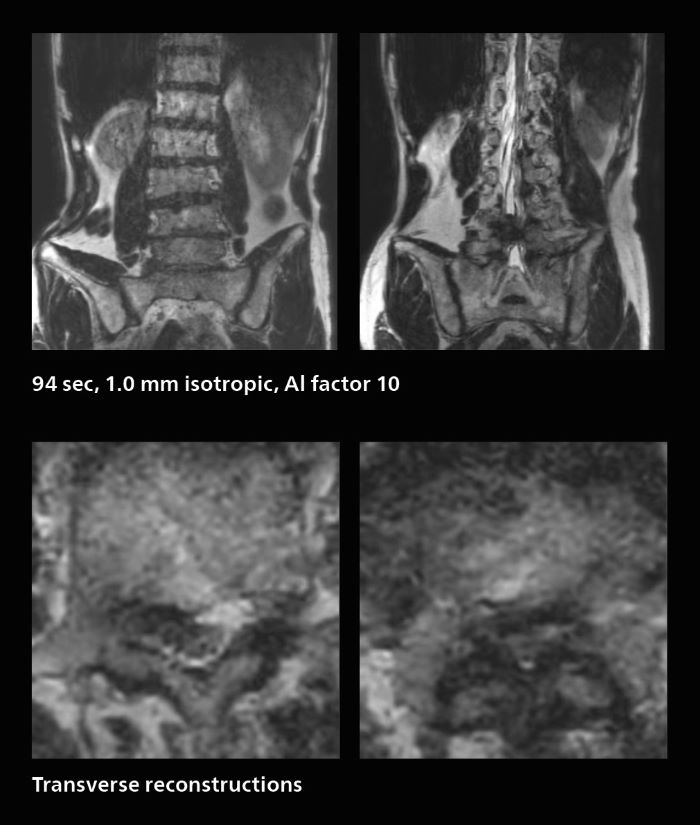

MRI of rectal cancer

In this patient MRI was done to help in diagnosing the depth of invasion. Performed on Elition X.

MRI of rectal cancer: fast isotropic 3D acquisitions providing excellent image quality with use of AI-enabled SmartSpeed

He also describes the benefit of being able to perform 3D diffusion-weighted imaging. “Previously, we only had DWI images in one direction to make a diagnosis. Now, we can do something that was not possible before: performing a DWI volume acquisition so that multiplanar reconstruction can be used, allowing us to look at scan results from all directions to make the diagnosis,” Dr. Katahira says.

“What used to be a diagnosis based on just cross-sectional images, can now be based on a volume image. This is a dramatic improvement for us, because it is now possible to look at slices in various cross section directions. For example, the presence or absence of venous invasion is very important in rectal cancer patients, because venous invasion can cause metastasis in the future. The ability to reconstruct images according to the direction of the blood vessels, allows us to see venous infiltration more realistically, which is a world of difference from what we were used to.”